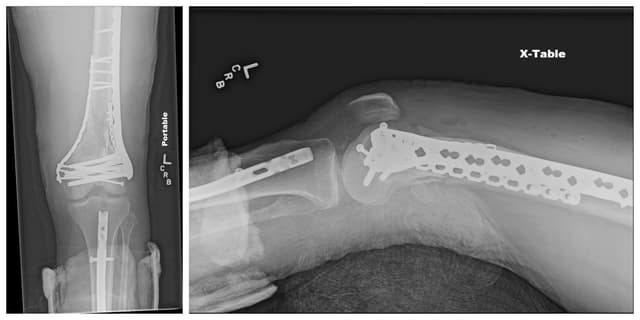

Pre-op

Post-op